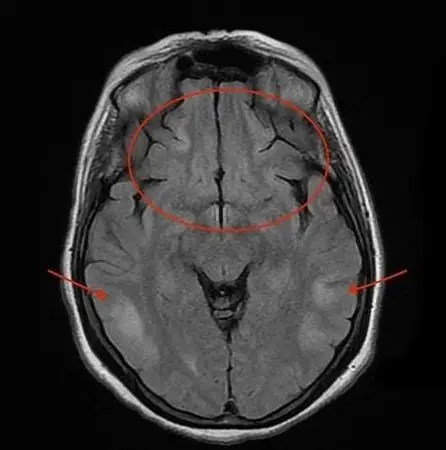

flair 示双侧额叶内侧,岛叶皮层(圈示)和颞叶后部(箭头)

图1 t2wi双侧额叶皮层异常信号